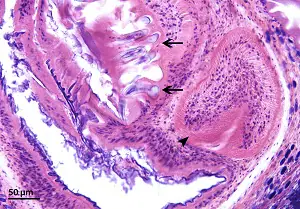

Taenia solium cysticerci in tissue sections

Taenia solium cysticerci (also called “cysticercus cellulosae”) are fluid-filled cystic structures consisting of a thin bladder wall and parenchymatous portion containing a single invaginated scolex surrounded by a convoluted spiral canal. The hooks of the armed scolex may be visible in tissue sections. Cysticerci are typically 5—15 mm long, but may reach up to 5 cm.

Figure C: T. solium cysticercus in swine muscle tissue, H&E stained. Note the armed scolex (arrow) and convoluted spiral canal (darts).

Figure D: Closer view of the the scolex portion of the T. solium cysticercus shown in Figure C. The refractile hooks (arrows) and one sucker (dart) are visible.